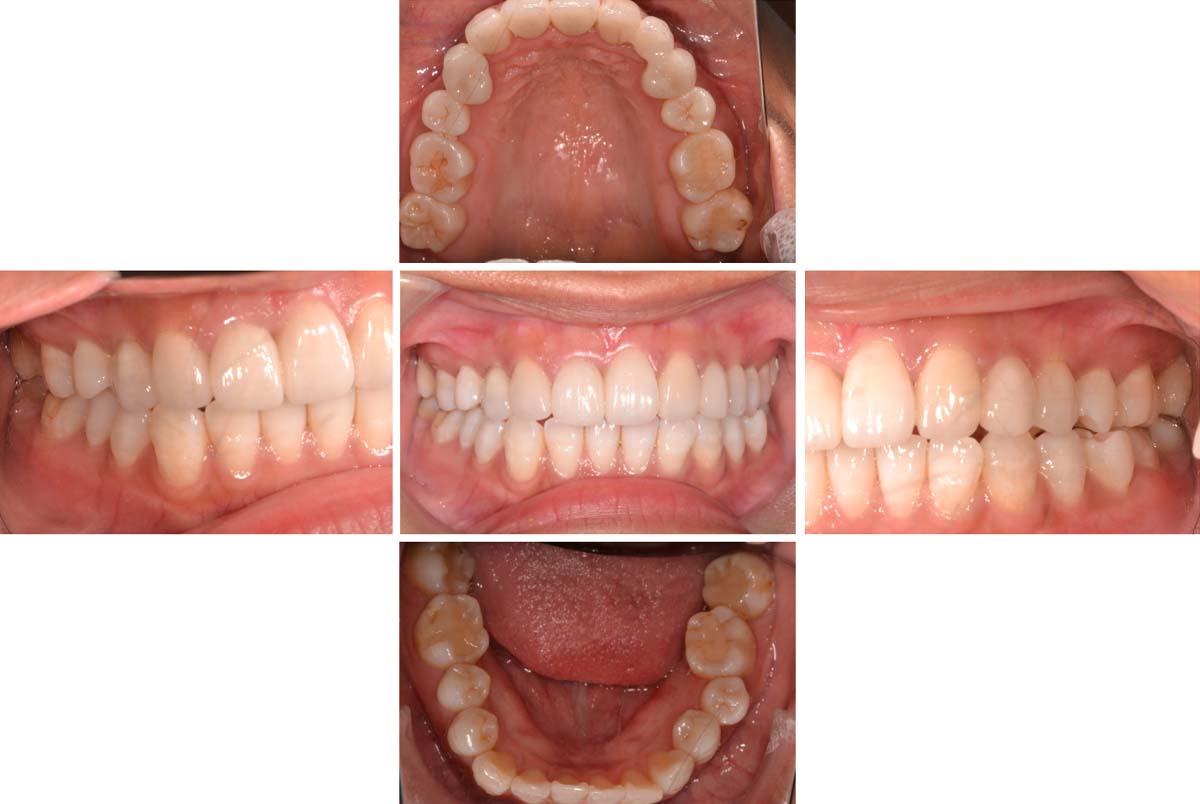

| 術後 |

年齢:33歳

主訴:前歯の黒ずみがきになる。奥歯に穴が開いている気がする。

医療面接、レントゲンや写真より、歯並びの問題と将来的に噛み合わせから顎関節症状がでてくる恐れがあると診断できました。そのため、矯正治療を含めた咬合治療をしていくことになりました。